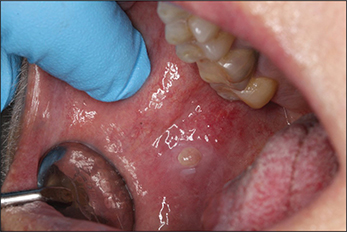

In September 2018, a follow-up showed a progressive exophytic growth on the tongue. New, firm, soft tissue changes in the mucous membrane on the right side of the buccal cheek, much like the previous changes seen on the tongue, were observed (Figure 11). This new growth was also noticeable on FDG PET/CT in August, a month before. The patient experienced pain mainly on the tongue, and thus, treatment with Rituximab was initiated.

Fig 10

Figure 11. In September of 2018, a new, firm lesion of the right buccal mucosa could be observed.

Approximately 1 year later, in 2019, the patient reported that she was completely pain-free. The lesions remained but were significantly less firm in consistency. Neither color change nor progression of the lesions were observed (Figure 12).

Fig 11

Figure 12. In 2019, the lesion of the tongue remains, however is painless, less firm and without colour change or obvious progression. The lesion of the right buccal mucosa remains unchanged.